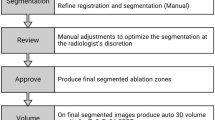

The steps of the HepACAGA technique are illustrated in Figs. 1 and 2. Patients were admitted on the day of ablation. Treatment was performed in an angiography suite under general anesthesia. General anesthesia was required in order to obtain apnea during the procedure. Patients were positioned supine, with an arms-down posture. Care was taken to position tubing and other lines in such a way that the C-arm could rotate around the patient unobstructed.

Schematic of the HepACAGA technique. Left panel: C-arm CT is obtained during contrast injection through a catheter placed in the hepatic artery. Left insert: tumor enhancement due to selective contrast injection. Right panel: the C-arm is automatically positioned in a way that the entry point and target are aligned (entry point view). The entry point and target are projected on the live fluoroscopy images. Right insert: positioning of the microwave antenna through the projected entry point into the target

Planning and Navigation

C-arm CT was checked for visualization of the target tumor, the presence of any new tumors, and the position of non-target structures (e.g., ribs, bowel, stomach, large veins, bile ducts). The needle trajectory was planned with C-arm navigation software (XperGuide, Philips, Best, The Netherlands) (see Fig. 3). Subsequently, the antenna was advanced in a straight line from the entry point to the target, under real-time fluoroscopy-guidance. Placement of the antenna was performed in apnea in order to mimic the position of the liver during planning-C-arm CT. Apnea was obtained by pausing the ventilator, allowing the lungs to deflate. After antenna placement, C-arm CT with hepatic arteriography was repeated to confirm correct placement. If the antenna had deviated from the planned trajectory, the antenna was repositioned.

navigation with XperGuide software (Philips). Left panel: entry point view in which the entry point (pink circle) and target (green circle) are projected on top of each other. The microwave antenna is now held directly in line with the projected needle path. Right panel: progress view showing the needle path at a 90 degree angle allowing for assessing needle depth